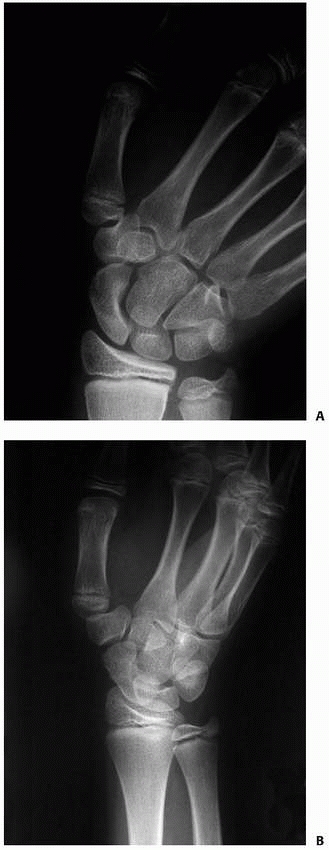

fractures in children are less common. The fracture configuration may

be transverse, spiral, or spiral oblique. The fracture may be

comminuted. Proximal phalangeal fractures usually are angulated in an

apex volar pattern because the distal fragment is extended by the

central slip and lateral band and the proximal fragment is flexed by

the intrinsic musculature (Fig. 8-25). Oblique

![]() |

|

FIGURE 8-25 A,B.

Lateral and oblique radiographs of a transverse proximal phalangeal fracture that demonstrates the characteristic apex volar deformity. |